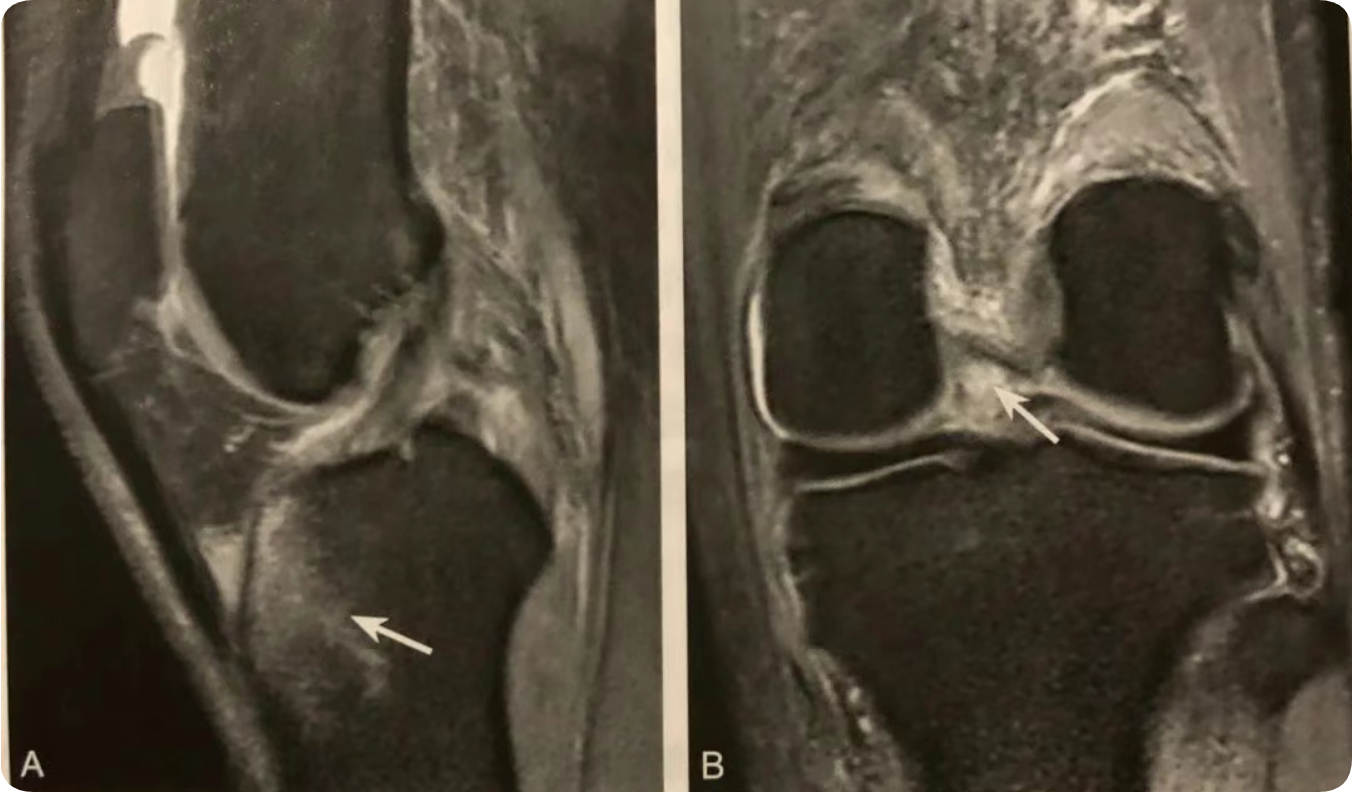

1. 内侧半月板桶柄状撕裂间接征象;

2. 在 MRI 矢状位观察;

3. 典型表现为两条近似平行的弧形低信号带;

4. 后上方者为后交叉韧带,前下方者为撕裂的半月板内缘碎片;

5. MRI 诊断注意结合病史和排外相关变异。